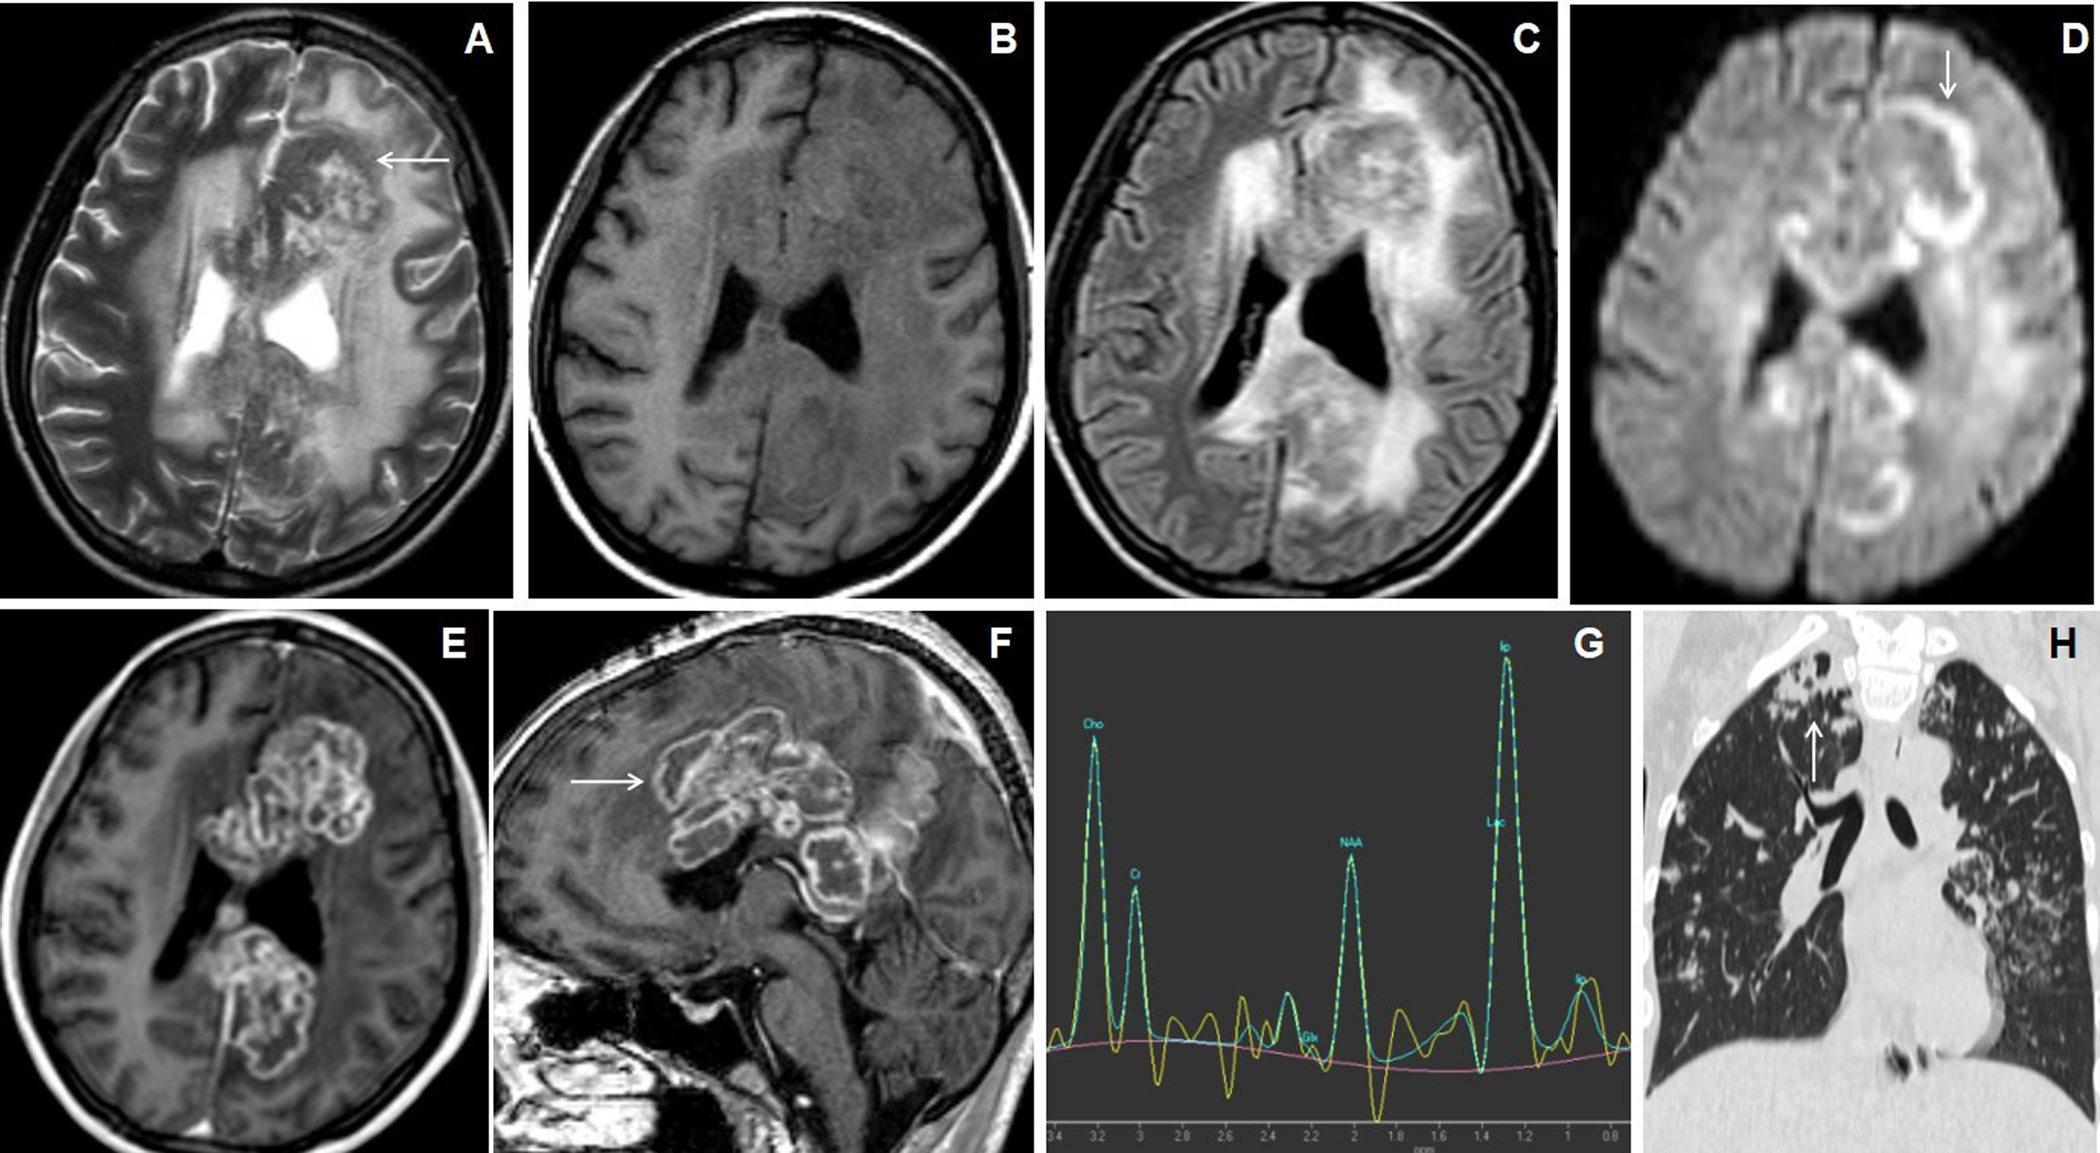

Figure 3. A 26 years female presented with gradually increasing headache and fever of 2 months duration. The cranial MRI with axial T2W image (A) shows irregular lesions with central T2 hyperintense core and peripheral hypointense wall (arrow) involving bilateral superior frontoparietal lobes in the para-falcine regions with grade-3 perifocal edema. Axial T1W image (B) shows hypointense central core and iso- to slight hyperintensities within peripheral wall. Axial FLAIR image (C) shows the involvement of the corpus callosum. Axial DWI image (D) shows irregular peripheral diffusion restrictions within wall (arrow). Axial and sagittal post-contrast images (E&F) show multiple conglomerated irregular peripherally enhancing lesions with central necrosis (arrow). MR spectroscopy (TE 144) image (G) shows a large lipid peak at1.3ppm with raised choline peak. HRCT coronal reconstructed (H) of the thorax shows an irregular cavitating lesion in the apical segment of right upper lobe of lung (arrow) with ill-defined scattered irregular nodules in both lung fields.

Figure 4. 18 years female presented with headache and vomiting. Axial T2W image (A) shows multiple conglomerated lesions with hyper- to mixed-signal intense central core and isointense peripheral walls in the right frontal lobe with grade-2 perifocal edema. Axial T1W image (B) shows central hypointense core and iso- to slight hyperintense peripheral wall. Axial DWI and ADC map images (C&D) show irregular target-appearing diffusion restrictions (arrow). Axial and sagittal post-contrast images (E&F) show multiple conglomerated irregular peripherally enhancing lesions with central necrosis (arrow). MR spectroscopy (TE 144) image (G) shows a large lipid peak at 1.3ppm.